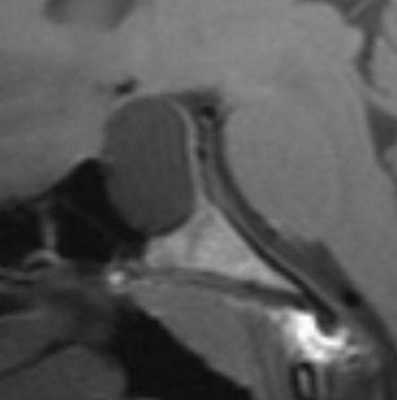

Коллоидная киста - это врождённое нейроэпителиальное образование. Коллоидная киста выстлана эпителием и имеет фиброзную капсулу. Она составляют около 1-2% объемных внутричерепных образований. Обычно диагностируются в возрасте между 30 и 50 годами. При МРТ головного мозга видно, что киста всегда расположена в переднее-верхнем отрезке III желудочка между отверстиями Монро. Контур ее четкий, форма округлая, содержимое бывает неоднородное. Размер от 3 мм до 4 см, при больших размерах она закрывает отверстия Монро и вызывает окклюзионную гидроцефалию. Сигнал зависти от примеси белка к ликвору. При наличии белкового мукоидного содержимого киста гиперинтенсивна на Т1-взвешенных МРТ и гипоинтенсивна на Т2-взвешенных МРТ, но встречаются варианты гиперинтенсивные на томограммах обоих типов кольцевидные или смешанные . Контрастирования не наблюдается.

Коллоидная киста - это врождённое нейроэпителиальное образование. Коллоидная киста выстлана эпителием и имеет фиброзную капсулу. Она составляют около 1-2% объемных внутричерепных образований. Обычно диагностируются в возрасте между 30 и 50 годами. Всегда расположена в переднее-верхнем отрезке III желудочка между отверстиями Монро. Контур ее четкий, форма округлая, содержимое бывает неоднородное. Размер от 3 мм до 4 см, при больших размерах она закрывает отверстия Монро и вызывает окклюзионную гидроцефалию. Сигнал зависти от примеси белка к ликвору. При наличии белкового мукоидного содержимого киста гиперинтенсивна на Т1-взвешенных МРТ головного мозга и гипоинтенсивна на Т2-взвешенных МРТ, но встречаются варианты гиперинтенсивные на МРТ головного мозга обоих типов взвешенности кольцевидные или смешанные. При МРТ головного мозга с контрастированием усиления сигнала не наблюдается.